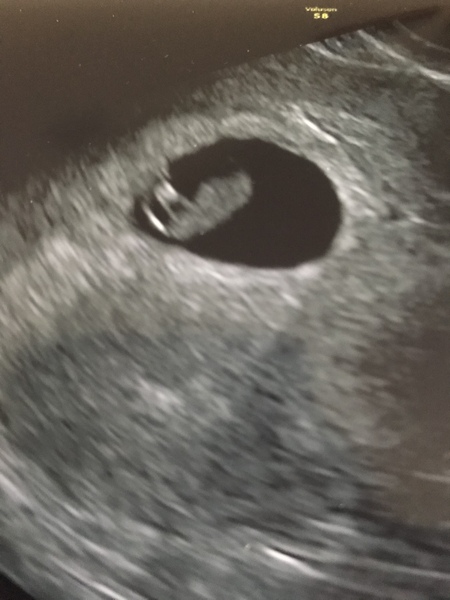

1sttimemamasel · 17/11/2019 15:56

I’ve had my early scan today and little bean is healthy and has strong heartbeat ❤️ Currently measuring at 7.5 weeks.

Had my early scan today and scan showed me 1 day ahead, 8+3 now.. healthy baby with strong heartbeat ❤️

I had my private early scan last night. Saw a baby in the right place with a lovely strong heartbeat 💓 feels a lot more real now! The scan put me 5 days ahead of what I’d thought so based on that I’m 8+5 with a new EDD of 25th June. I guess it’s still probably liable to change again!